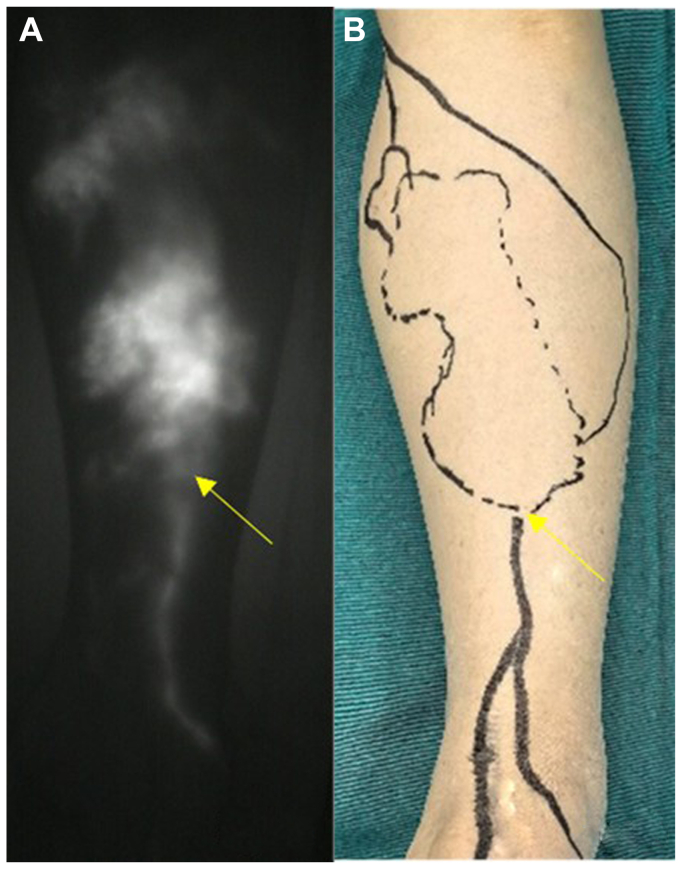

Lower limb lymphedema (LLL) is a chronic condition with impaired lymphatic drainage. Lymphaticovenular anastomosis (LVA) is a promising microsurgical treatment for LLL. Refined surgical techniques, such as optimal incision placement and precise lymphatic vessel identification, are essential for better clinical outcomes. For patients with LLL, we performed an LVA via the lymphosome-based four-incision approach. We standardized incision positioning and identified lymphatic vessels for LVA to improve surgical outcomes.

A retrospective study was conducted on 59 patients with LLL who underwent LVA. Among them, 32 patients in the study group received LVA using the four-incision approach, and 27 patients in the control group underwent LVA with empirically determined incision placement. All patients were followed up for 12 months after the operation. The outcome measures included the number of lymphatic-to-venous anastomoses, surgical duration, Lymphedema Functioning, Disability, and Health Questionnaire for Lower Limb Lymphedema and Lower Extremity Lymphedema Index, Patient Health Questionnaire-9 items, and subcutaneous thickness.